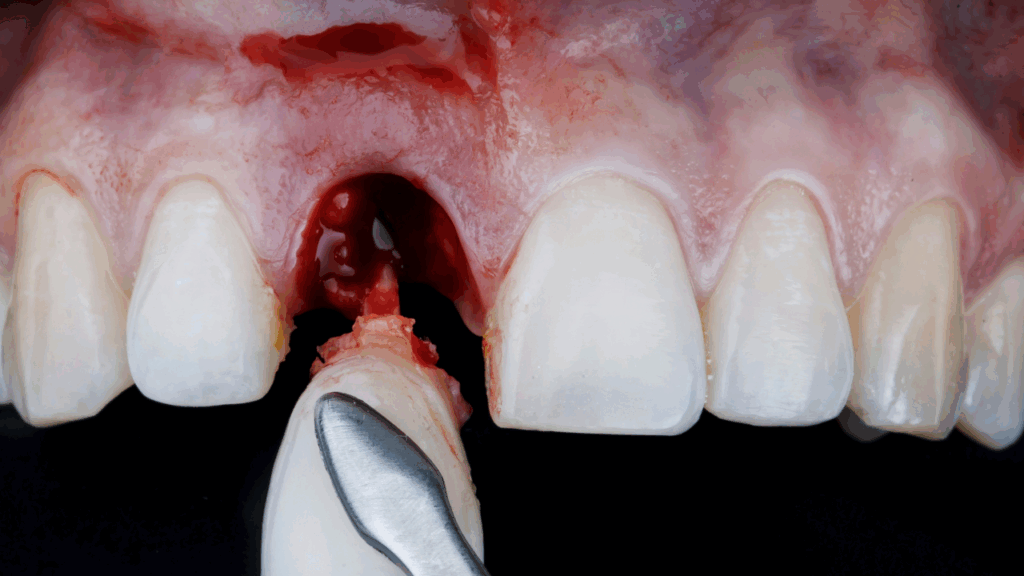

A single dental implant is a titanium post that replaces the root of a missing tooth. It’s surgically placed into your jawbone and topped with a custom-made crown that looks just like your natural tooth.